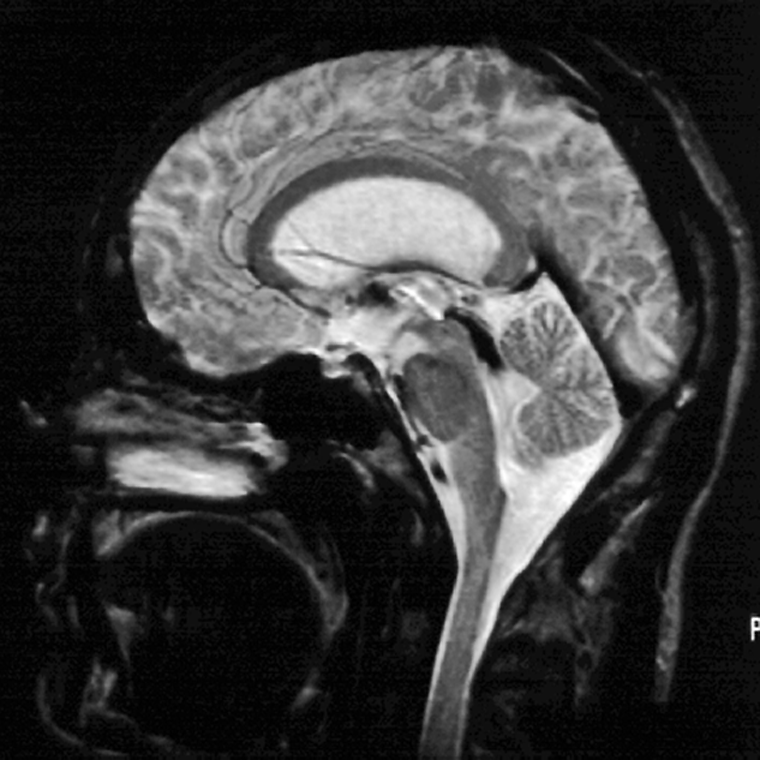

Figura 14-03:

Patient with hydrocephalus. On this T2-weighted SE image, CSF should be bright. How­ever, due to flow ef­fects, CSF in the aqueduct and the upper fourth ventricle appears dark.